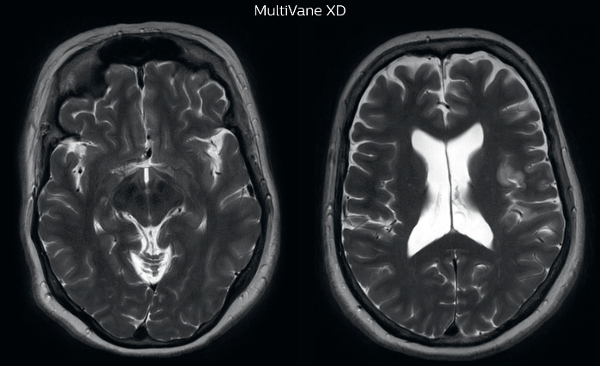

The images made with MultiVane XD show significant reduction in motion artifact compared to the T2-weighted images without MultiVane below them. Scanned on Ingenia 3.0T